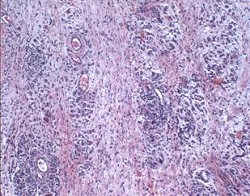

May 2017 article, Drs. Simon Tappin (right), Kate Murphy at

Langford House, UK, report a case of a 4 month old female cavalier King

Charles spaniel with "episodic facial swelling, progressive inability to

open the jaw, and exopthalmia. During these episodes, the masticatory

muscles appeared to swell and became firm and painful." Clinical

examination revealed bilateral swelling of the masseter muscles, slight

bulging of the eyes and discomfort on palpation of the masticatory

muscles. Her jaw opening was limited. Biopsy of the masseter muscles

revealed inflammation, myfiber loss, edema, and fibrosis. (See image

at left.) The dog also was diagnosed with a Neospora infection,

suspected as a trigger for the

Muscle biopsies: Biopsies were taken from the masseter and temporalis

muscles. These

revealed

multifocal areas of mononuclear cell infiltration composed of scattered

macrophages and clusters of lymphocytes, generalized myofiber loss and

atrophy, fibrosis and edema. (See image at right.)